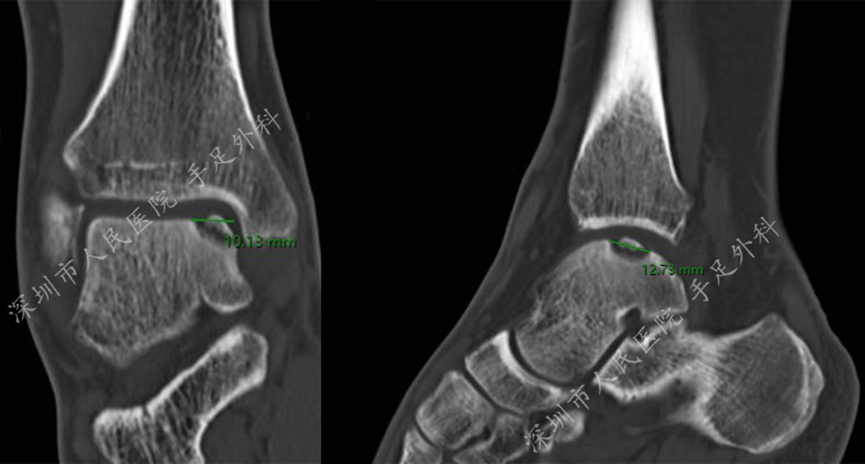

图8:CT示距骨软骨损伤及损伤范围测量